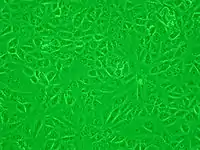

Vero cell

Vero cells are a lineage of cells used in cell cultures.[1] The 'Vero' lineage was isolated from kidney epithelial cells extracted from an African green monkey (Chlorocebus sp.; formerly called Cercopithecus aethiops, this group of monkeys has been split into several different species). The lineage was developed on 27 March 1962, by Yasumura and Kawakita at the Chiba University in Chiba, Japan.[2] The original cell line was named "Vero" after an abbreviation of verda reno, which means "green kidney" in Esperanto, while vero itself means "truth" in Esperanto.[3]

The Vero cell lineage is continuous and aneuploid, meaning that it has an abnormal number of chromosomes. A continuous cell lineage can be replicated through many cycles of division and not become senescent.[4] Vero cells are interferon-deficient; unlike normal mammalian cells, they do not secrete interferon alpha or beta when infected by viruses.[5] However, they still have the Interferon-alpha/beta receptor, so they respond normally when recombinant interferon is added to their culture media.